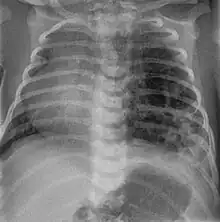

CPAM on chest radiograph in a newborn. Large cystic changes in the left lung, leading to a mediastinal shift to the right due to their mass effect.

CPAMs are often identified during routine prenatal ultrasonography. Identifying characteristics on the sonogram include: an echogenic (bright) mass appearing in the chest of the fetus, displacement of the heart from its normal position, a flat or everted (pushed downward) diaphragm, or the absence of visible lung tissue.

CPAMs are classified into three different types based largely on their gross appearance. Type I has a large (>2 cm) multiloculated cysts. Type II has smaller uniform cysts. Type III is not grossly cystic, referred to as the "adenomatoid" type. Microscopically, the lesions are not true cysts, but communicate with the surrounding parenchyma. Some lesions have an abnormal connection to a blood vessel from an aorta and are referred to as "hybrid lesions."